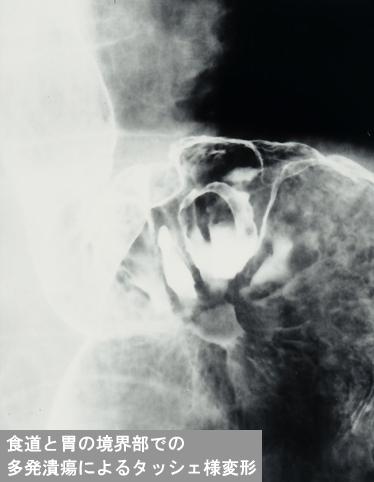

[Image-ID:12207]